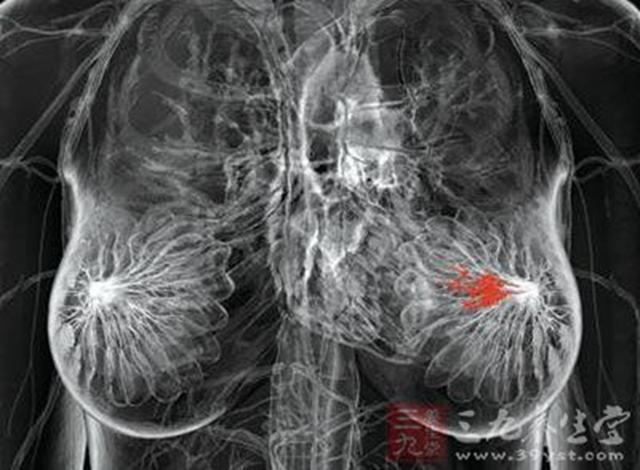

3Her-2基因检测意义

研究表明,HER220%~30%的原发性乳腺浸润性导管癌中存在基因的扩增和蛋白的过度表达。这些HER2阳性的肿瘤是一种高危肿瘤,对某些常规的化疗和激素治疗反应性差,肿瘤浸润性强,无病生存期短,预后差。为此,多种阻断HER2的抗癌药物相继问世,其中目前最为常用并经FDA批准的此类药物是曲妥珠单抗(赫赛汀),适用于治疗HER2过度表达的乳腺癌,因此准确评价HER2基因和蛋白水平是至关重要的,NCCN指南强调,仅HER2过表达(或基因扩增)的患者才能从赫赛汀的治疗中获益。。